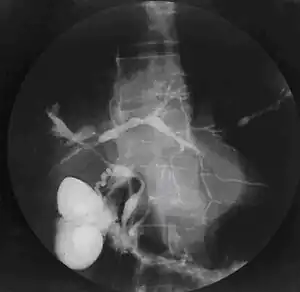

| Cholangiogram of primary sclerosing cholangitis. | |

Historically, a cholangiogram would be obtained via endoscopic retrograde cholangiopancreatography (ERCP), which typically reveals "beading" (alternating strictures and dilation) of the bile ducts inside and/or outside the liver. Currently, the preferred option for diagnostic cholangiography, given its non-invasive yet highly accurate nature, is magnetic resonance cholangiopancreatography (MRCP), a magnetic resonance imaging technique. MRCP has unique strengths, including high spatial resolution, and can even be used to visualize the biliary tract of small animal models of PSC.[18]